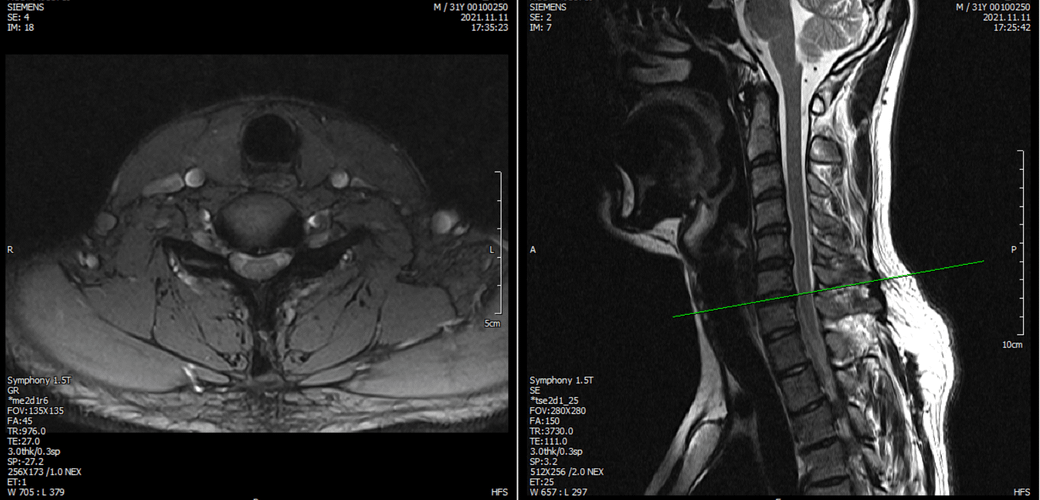

※우리들병원 (신경외과 대표원장) : 경추,요추 MRI 촬영했고 요추는 매우 건강하고 경추에는 일자목에 퇴행성 디스크가 보이지만 한쪽팔에 저림이나 힘빠짐을 유발할 정도는 절대아니고, 다른 원인을 찾아야한다고 했습니다.

※분당서울대병원 재활의학과 : 근전도검사 이상없음, 경추 요추 MRI를 봐도 근골격계 문제로 보기 어렵다. 신경계 문제도 아니다.

※분당서울대병원 신경과 : 근전도에 경추,요추,뇌 MRI를 다 했으니 할만한 검사는 다했고, 디스크가 아예 없는 것은 아니기 때문에 디스크 증상일 가능성이 있음, 주사치료 받아보는 것 권유, 과반사(DTR항진) 있으나 정상범주.

3명이 디스크가 아니라고 하는데 1명이 디스크일수 있다고 하니까 조금 어렵습니다. 경추디스크가 약간은 있으니 팔저림은 설명할수 있다해도 다리저림은 설명이 안됩니다.. MRI 결과상 요추는 매우 건강하다고 하셨거든요.

아래는 저의 경추과 요추 MRI 사진 첨부합니다.